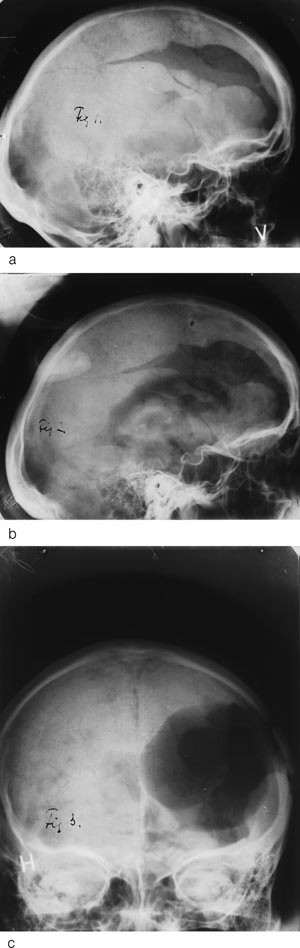

Fra 1947 viet Monrad-Krohn dette feltet særlig interesse og publiserte flere artikler frem til han døde (10, 11). Den gjeveste ble publisert allerede i desember 1947 i tidsskriftet Brain. Denne artikkelen brakte den mest utførlige gjennomgangen av sykehistorien og var basert på en forelesning gitt i National Hospital i London (12) (fig 2a – c).